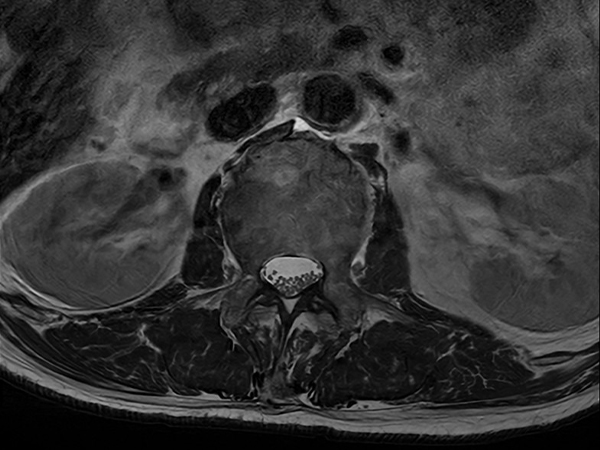

Axial T2w TSE